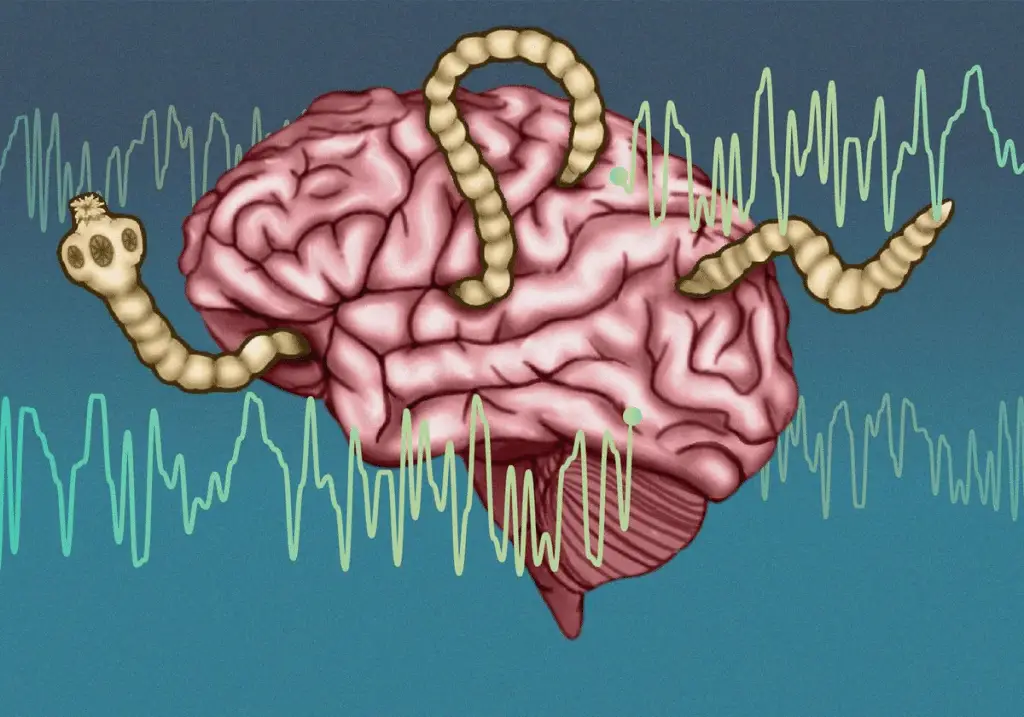

Il team guidato dalla neuroscienziata Tajie Harris ha studiato il comportamento delle cellule T CD8+, una tipologia di linfociti specializzati nell’eliminare cellule infette.

La sorpresa è arrivata quando i ricercatori hanno scoperto che Toxoplasma può infettare anche le cellule T CD8+ stesse.

A questo punto emerge una domanda critica: se il parassita può invadere le cellule che dovrebbero eliminarlo, perché l’infezione non sfugge sempre al controllo?

In sostanza, se una cellula T CD8+ viene infettata da Toxoplasma, può attivare un meccanismo di autodistruzione mediato dalla caspasi-8.

Per il parassita è un problema enorme: Toxoplasma ha bisogno di vivere all’interno di cellule ospiti. Se la cellula muore, l’infezione si interrompe.

L’analisi dei tessuti cerebrali ha mostrato che, in assenza di caspasi-8, le cellule T CD8+ risultavano molto più frequentemente infettate.

Il dato suggerisce che la capacità di autodistruzione delle cellule infette è un meccanismo cruciale per proteggere il cervello.